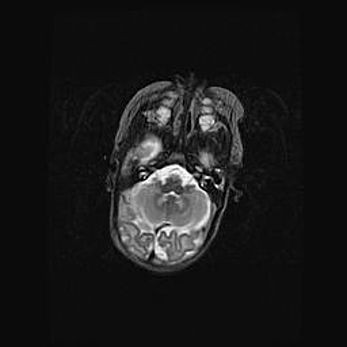

Подострая гематома правой гемисферы мозжечка.

Наружная гидроцефалия.

Возраст: 15 дней

Вес: 3100 г

Пол: женский

Окружность головы: 37 см

Срок гестации: 35-36 недель

При открытой наружной форме гидроцефалии у новорожденных расширяются и переполняются субарахноидные пространства.

Кровоизлияния в мозжечок имеют две клинико-анатомические формы: полушарные гематомы и кровоизлияния в червь.

К появлению этой патологии может привести: повреждения головного мозга, возникающие в результате асфиксии и гипоксии плода при беременности, или травмы во время родов. Редко гематома мозжечка может быть результатом первичной коагулопатии и сосудистой мальформации, диссеминированном внутрисосудистом свертывании, изоиммунной тромбоцитопении.